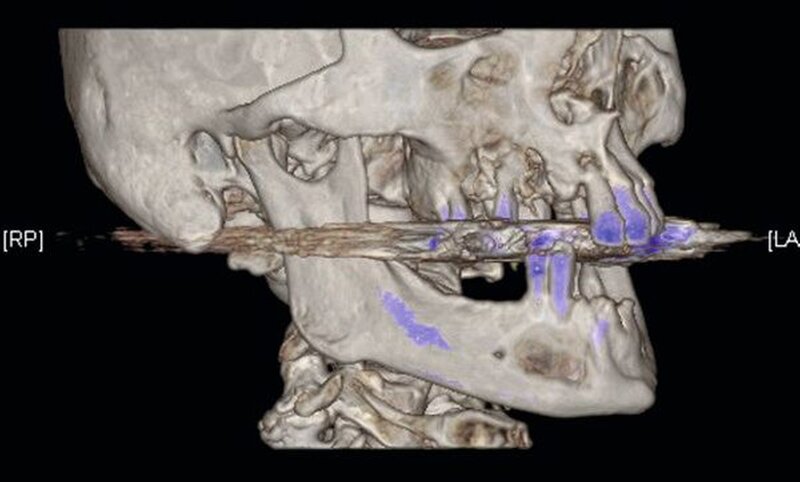

Die Computertomografie der Nasennebenhöhlen (NNH-CT) (nativ) zeigte dann das Ausmaß der knöchernen Destruktion. Neben der ausgedehnten generalisierten Nekrose des Oberkiefers konnte nebenbefundlich eine zystische Läsion im Bereich des Unterkiefers Regio 41 bis 45 diagnostiziert werden. Voraussichtlich ging diese vom Wurzelrest des Zahnes 41 aus. Weiterhin bestand eine totale Verschattung beider Sinus maxillaris und eine akzentuierte Lymphadenopathie in allen abgebildeten Leveln.